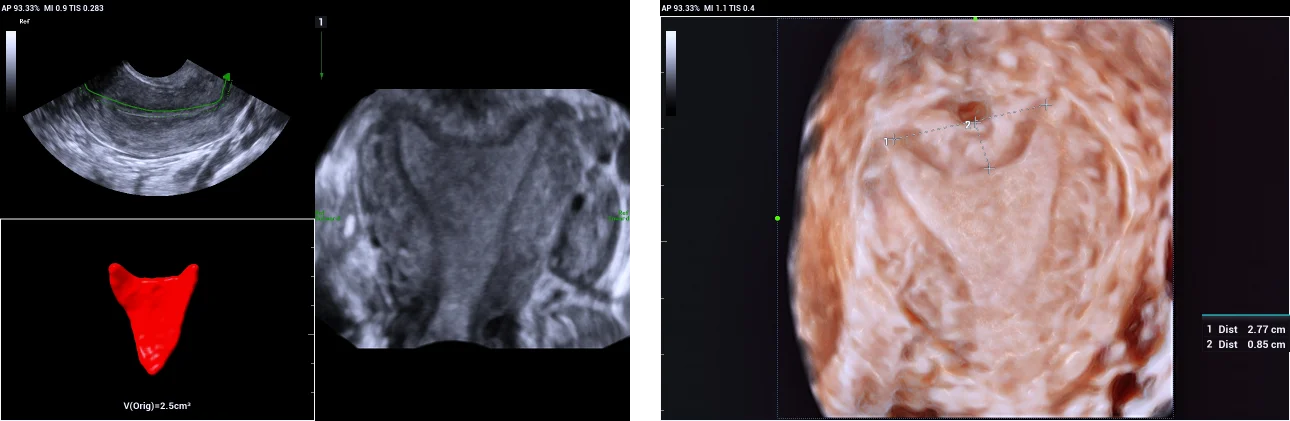

4. Subseptate uterus.

Use of Smart ERA in diagnosis of Mullerian duct abnormalities - Subseptate uterus

The fundal indentation was an acute angle at the central point > 1.5 cm deep. Using iPage+ clearly illustrates the extent of fundal indentation and the single cervix and vagina.